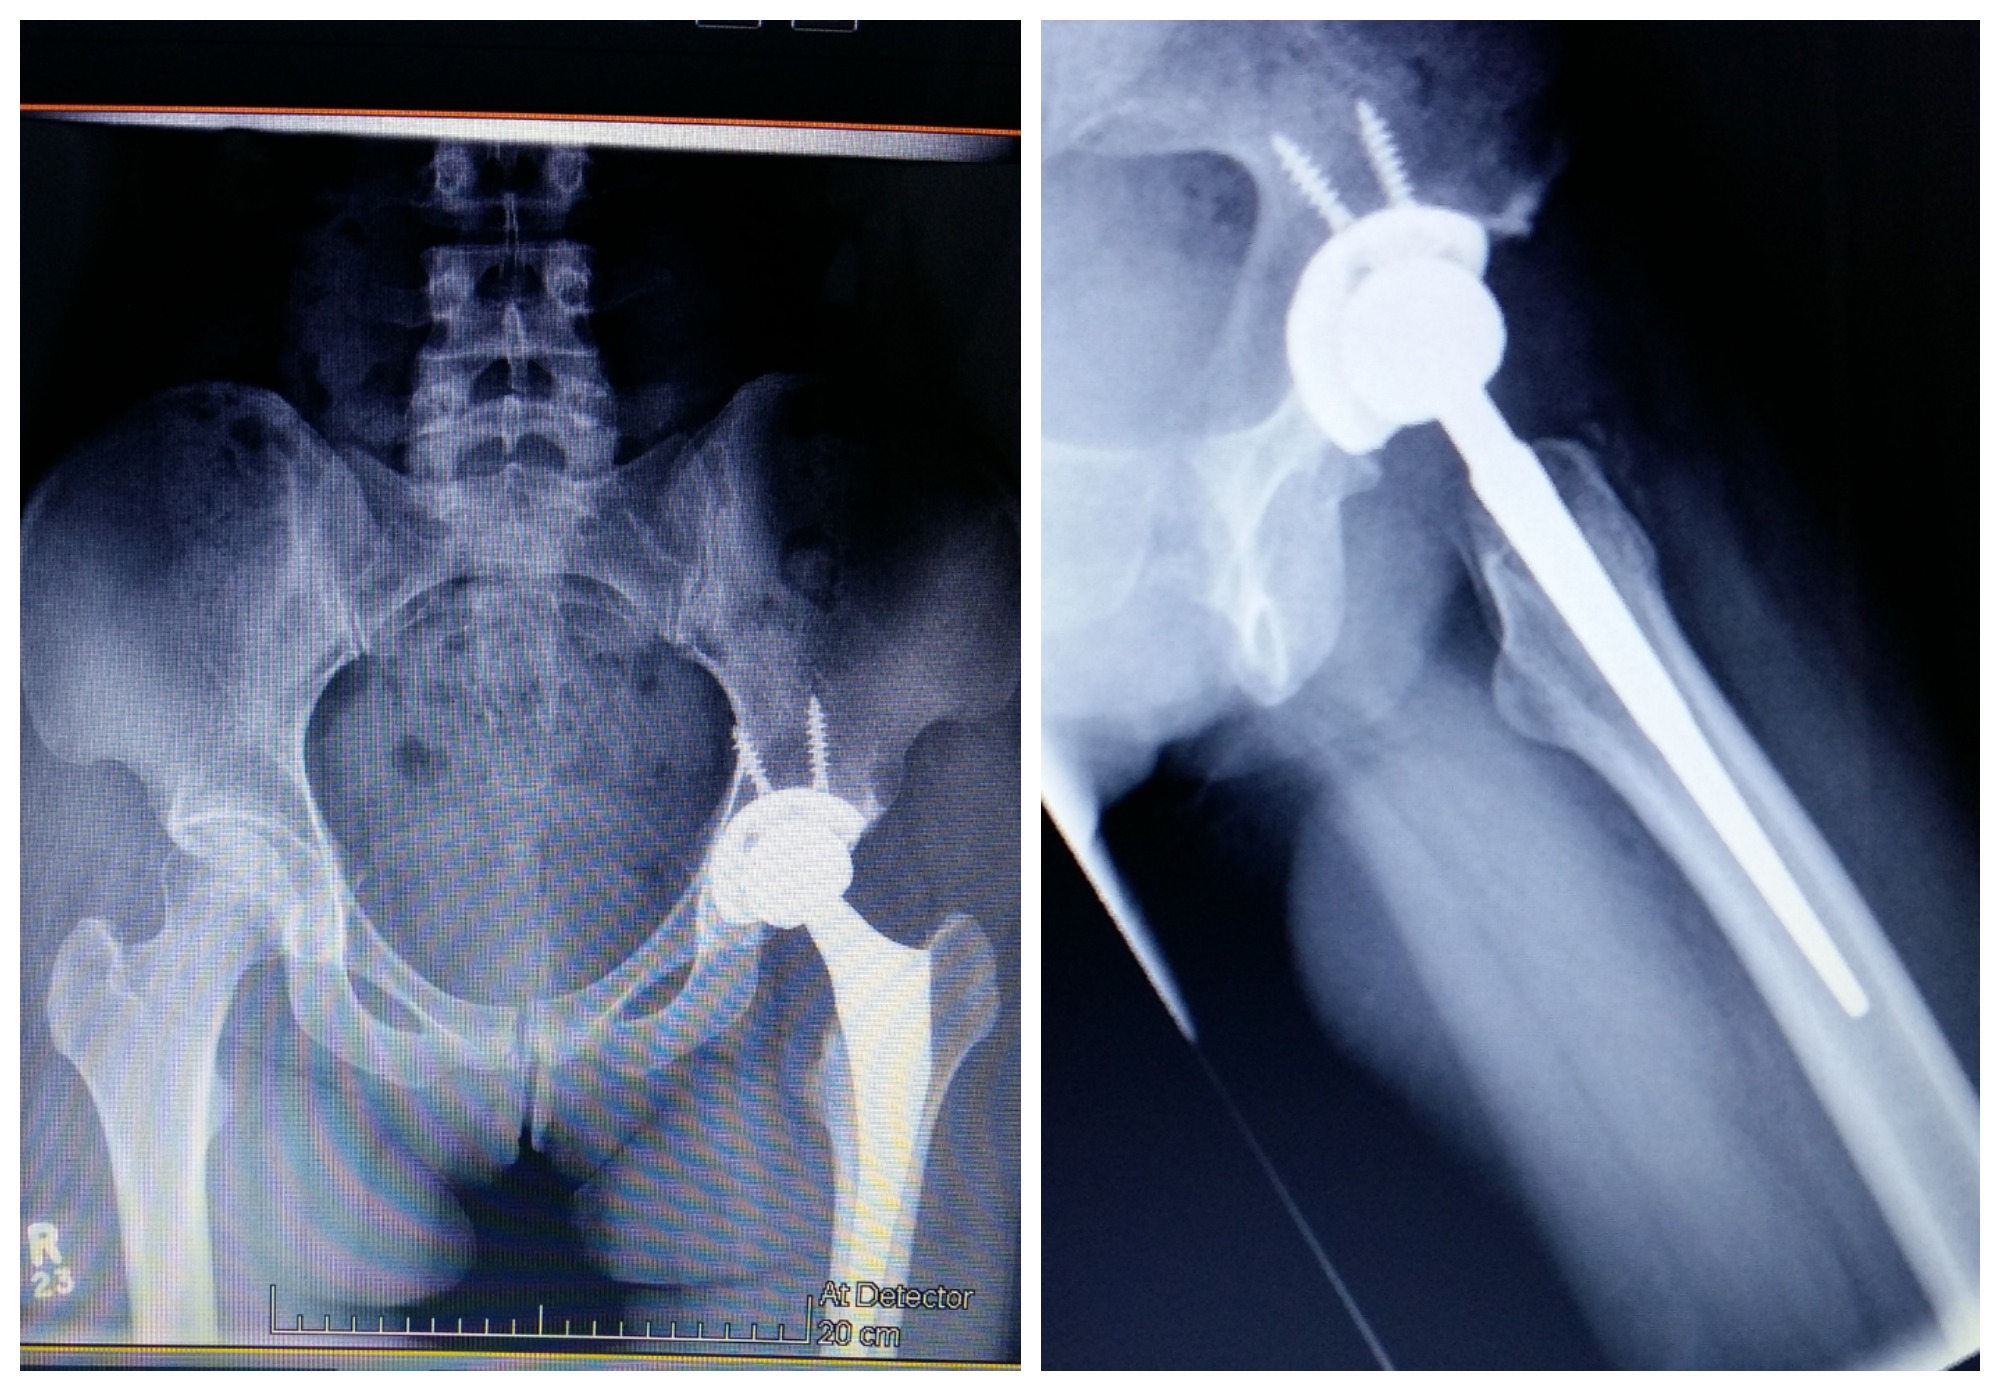

Computers at the back of the room had all different types of x-rays for different patients. I was given a bed in the back corner of the room right next to the computers. As we waited, a hip replacement image came up on the screen and I looked over at my mom and said, “Look at how beautiful that hip looks! It’s amazing what science can do these days.”

My surgeon was looking at the screen and then walked over to my bed. He looked at me and said, “Your hip looks great! How are you feeling?”